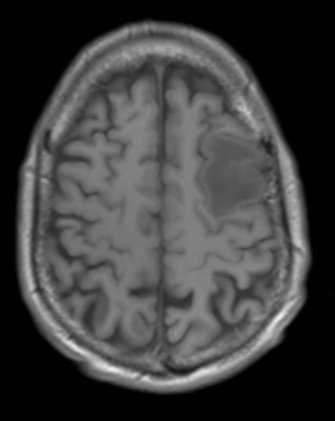

Washington University Experience | INFECTION | Bacteria | Abscess | Abscess, Early (Cerebritis - Initial Wall Formation) | 5A2 (Case 5) T1noC - Copy

5A2,3 These T1-weighted scans without (5A2) and with (5A3) contrast shows a rim enhancing nodule with marked surrounding edema.